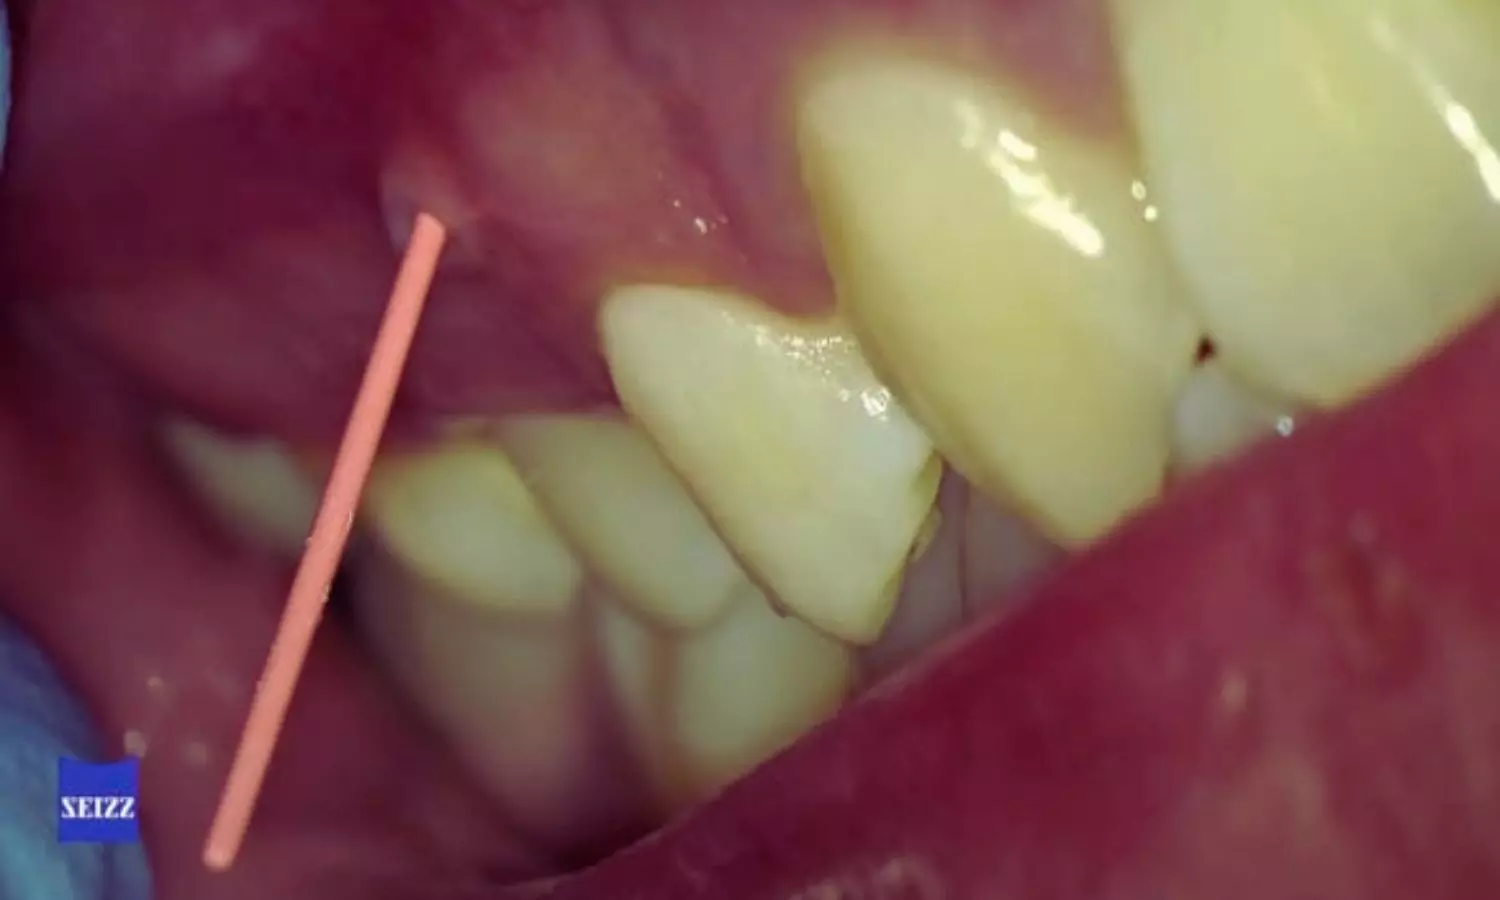

Brazil: The combination of periapical radiography (PR) and cone-beam computed tomography (CBCT) significantly improves diagnostic accuracy for both endodontists and periodontists. This integrated approach provides more reliable detection and assessment of complex cases compared to PR alone, supporting better clinical decision-making and interdisciplinary collaboration.

- Adding CBCT to periapical radiography markedly improved diagnostic accuracy, increasing correct diagnoses from 42.2% with PR alone to 67.2% with the combined approach.

- When CBCT was available, both endodontists and periodontists achieved a diagnostic accuracy of 58.8%.

- The PR+CBCT combination was especially effective in identifying endo-periodontal lesions, including cases with and without associated root damage, compared with periapical radiography alone.